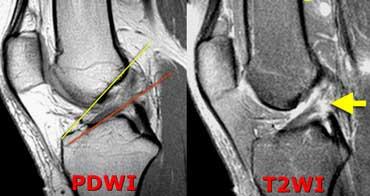

TRÁI: Các bó sợi ACL có hướng bình thường nhưng không bám vào lồi cầu đùi. PHẢI: Dấu hiệu hõm rỗng: dịch áp sát mặt trong lồi cầu ngoài.

Đôi khi dễ đánh giá hơn liệu các bó sợi có còn bám vào xương hay không khi quan sát trên mặt phẳng vành.

Tuyệt đối không được có dịch áp sát mặt trong lồi cầu ngoài.

Nếu có dịch ở vị trí này, được gọi là ‘dấu hiệu hõm rỗng’, cho thấy ACL đã bị bong khỏi điểm bám trên lồi cầu đùi.

Trên mặt phẳng ngang có dấu hiệu hõm rỗng (mũi tên vàng) ở vị trí lẽ ra ACL phải bám vào lồi cầu. Ở mức thấp hơn (sang phải), ACL đứt đã dính sẹo vào PCL (mũi tên xanh lá).

Trên mặt phẳng ngang cũng phải thấy dây chằng nằm sát bên lồi cầu.

Ở mức thấp hơn, chúng ta thấy ACL đứt bám dính vào dây chằng chéo sau.

Chúng đã dính vào nhau thành sẹo.

Đây là hình ảnh rất thường gặp trong đứt ACL mạn tính.

Sự dính sẹo này tạo ra góc gấp cấp tính của dây chằng.

Mặc dù ACL đã dính vào PCL, nhưng vẫn không đủ vững và cần phải tái tạo.